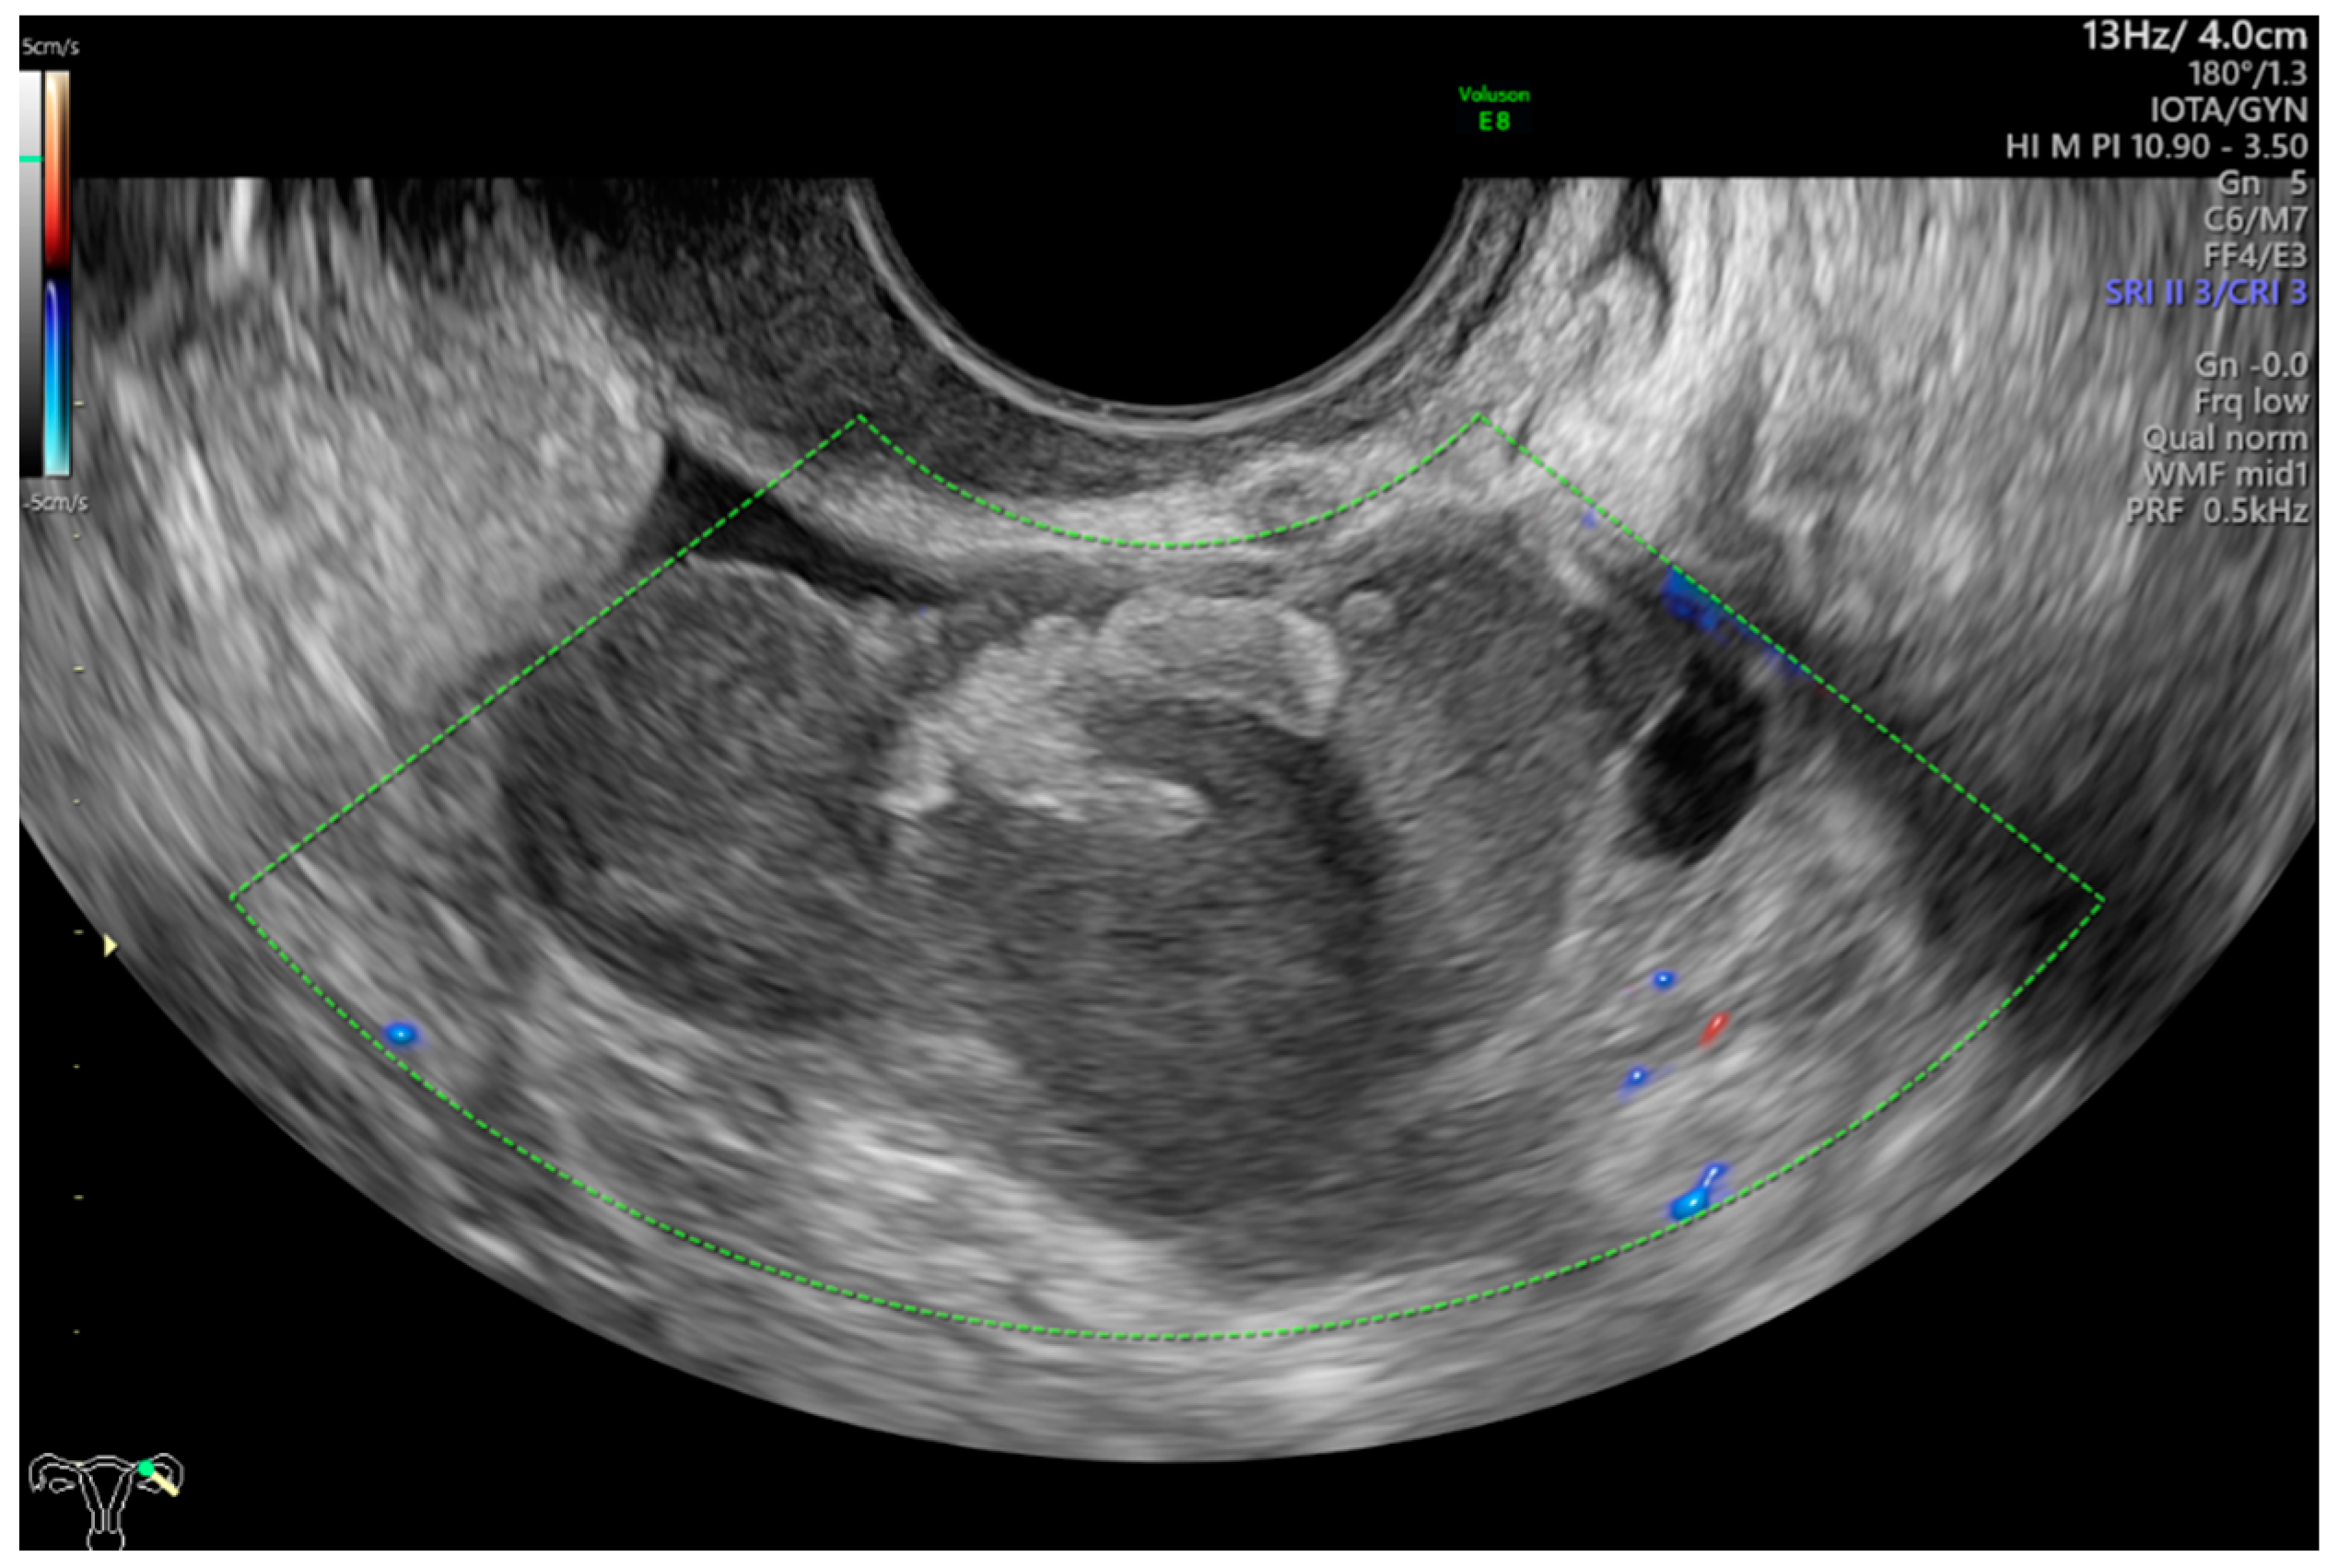

- Timmerman, D.; Valentin, L.; Bourne, T.H.; Collins, W.P.; Verrelst, H.; Vergote, I.; International Ovarian Tumor Analysis (IOTA) Group. Terms, definitions and measurements to describe the sonographic features of adnexal tumors: A consensus opinion from the International Ovarian Tumor Analysis (IOTA) group. Ultrasound Obstet. Gynecol. 2000, 16, 500–505. [Google Scholar] [CrossRef]